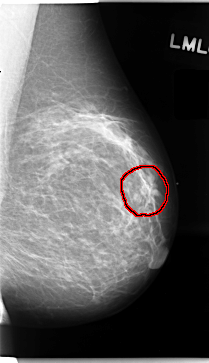

C_0059_1.LEFT_MLO

LEFT_MLO LINES 4712 PIXELS_PER_LINE 2712 BITS_PER_PIXEL 12 RESOLUTION 50 OVERLAY

FILE: C_0059_1.LEFT_MLO.OVERLAY

TOTAL_ABNORMALITIES 1

ABNORMALITY 1

LESION_TYPE MASS SHAPE IRREGULAR MARGINS SPICULATED

ASSESSMENT 5

SUBTLETY 4

PATHOLOGY MALIGNANT

TOTAL_OUTLINES 1

BOUNDARY